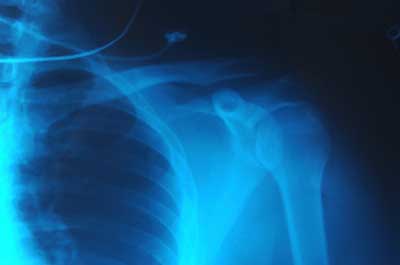

Roentgen的卓越发现成为人类历史上最重要的医学进步之一。X射线技术可让医生直观地观察人体组织,非常轻松地检查破骨,蛀孔和吞咽物体。可以使用修改的X射线程序来检查较软的组织,例如肺,血管或肠。

一般来说,医生将电影形象保持为负面。也就是说,暴露于更多光线的区域显得更暗,并且暴露于较少光线的区域显得更轻。硬质材料(如骨头)呈现白色,较软的材料显示为黑色或灰色。医生可以通过改变X射线束的强度来将不同的材料聚焦。